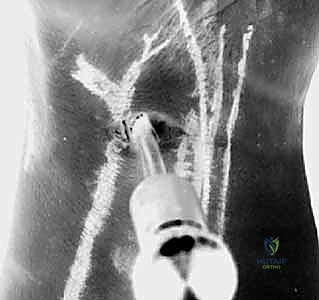

4. The Outside-In DRCL Repair Technique

"Now for the repair itself. We'll utilize an outside-in technique, which I find technically easier and more reproducible than the original inside-out method. Our goal is to reapproximate the torn DRCL to the dorsal capsule and its attachment sites, preventing impingement and restoring stability."

- Suture Passage - First Limb:

- "Through the 4-5 portal, we'll insert a curved 21-gauge spinal needle. Under direct arthroscopic visualization from the VR portal, carefully guide the tip of the needle to pierce the torn edge of the DRCL. Aim to capture a good bite of healthy, robust tissue."

- "Once the needle is through the ligament, advance it further until it exits the skin dorsally, adjacent to the 4-5 portal. Ensure it's not piercing any extensor tendons."

- "Thread one end of a 2-0 absorbable suture (e.g., PDS II or Vicryl) through the eye of this spinal needle."

- "Now, carefully withdraw the spinal needle, bringing the suture limb out through the skin incision of the 4-5 portal."

Figure 2C: Insertion of a curved spinal needle through the edge of the DRCL tear, guided by arthroscopic visualization.

- Suture Passage - Second Limb (Loop Formation):

- "Next, we'll repeat the process. Insert a second curved 21-gauge spinal needle, again through the 4-5 portal. This time, aim to pass it through a slightly different, but still healthy, part of the torn DRCL, creating a loop. The goal is to encircle the torn segment or bring its edges together."

- "Alternatively, you can use the same needle, re-inserting it. Pass the second limb of the 2-0 absorbable suture through this second needle."

- "Once the second limb of the suture is through the ligament, retrieve it using a suture grasper or snare inserted through the 3-4 portal. This creates a loop within the joint, encircling the torn DRCL."

Figure 2D: Illustrates the outside-in technique using two spinal needles and a suture retriever to pass and retrieve the suture limbs, forming a loop around the torn ligament.